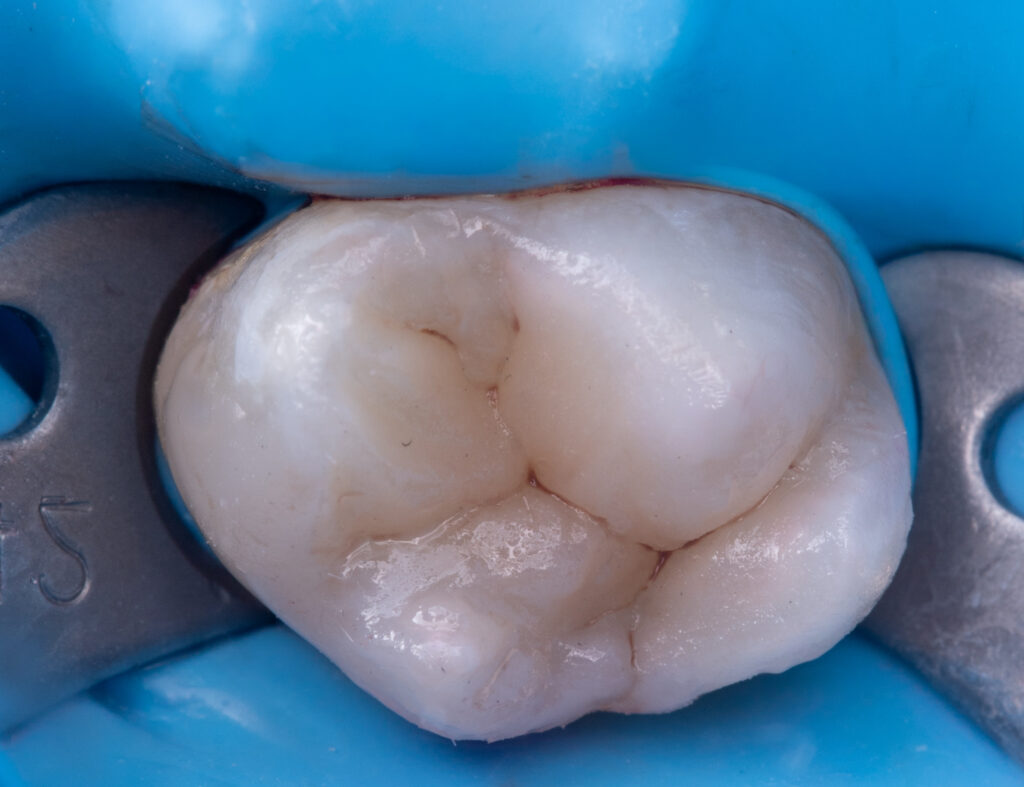

The patient presented with complaints of pain when consuming sweets in tooth 2.7.

A cold test (to determine whether the tooth was vital) and a periapical X-ray were performed before treatment. The patient could open the mouth only up to two fingers wide, which created difficulties with tooth restoration and rubber dam adaptation. EverX Bulk Fill was used due to the large cavity size to help prevent fractures. The enamel surface was restored using NeoSpectra A2 and Asteria A1B.